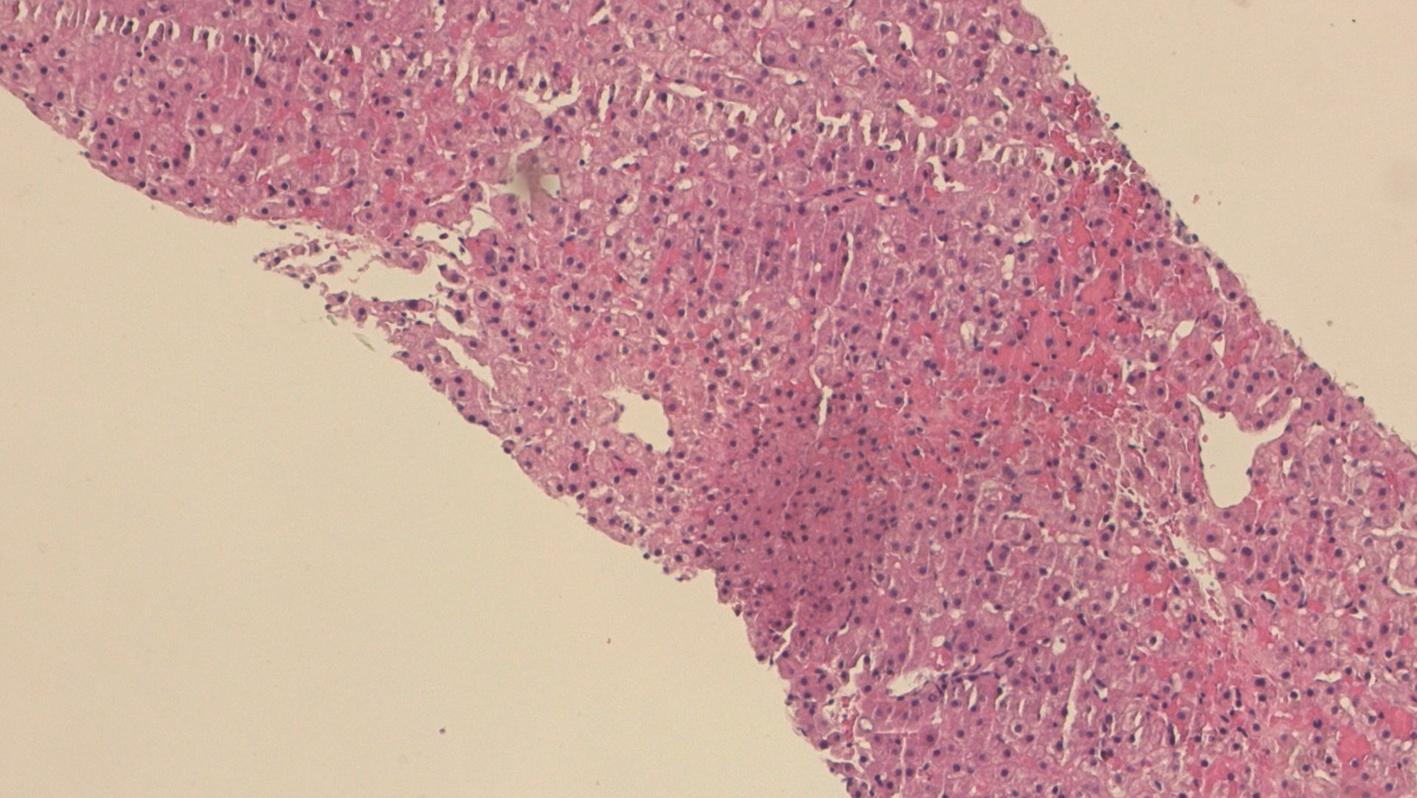

Selection of treatment regimens for pancreatic duct stones: A comparative analysis

Jinbin DONG, Weibing FANG, Yihai SHI

2022, 38(11): 2558-2564. DOI: 10.3969/j.issn.1001-5256.2022.11.023

Abstract(839) HTML (936) PDF (2050KB)(88)

Abstract:

Objective  To investigate the clinical efficacy of endoscopic retrograde cholangiopancreatography (ERCP), laparoscopy, and laparotomy in the treatment of pancreatic duct stones (PDS) by collecting related clinical data, to summarize the experience in selecting treatment regimens for PDS, and to further explore feasible treatment regimens that could maximize and optimize the benefits of PDS patients.  Methods  A retrospective analysis was performed for the clinical data of 131 PDS patients who were treated in Gongli Hospital Affiliated to Naval Medical University from June 2014 to December 2018, and according to the surgical procedure, they were divided into ERCP group with 69 patients, laparoscopy group with 32 patients, and laparotomy group with 30 patients. Related indices were monitored before and after treatment, and surgical outcome was compared between the laparoscopy group and the laparotomy group. The independent samples t-test was used for comparison of normally distributed continuous data between two groups; a one-way analysis of variance was used for comparison between multiple groups, and the least significant difference t-test or the SNK-q test was used for further comparison between two groups. The Mann-Whitney U test was used for comparison of continuous data with skewed distribution between two groups, and the Kruskal-Wallis H test was used for comparison between multiple groups. An repeated measures analysis of variance and the Friedman test were used for comparison of related indices before and after surgery, and the chi-square test was used for comparison of categorical data between groups.  Results  Among the 131 PDS patients, there were 40 patients with type Ⅰ PDS, 76 with type Ⅱ PDS, and 15 with type Ⅲ PDS. There was no significant difference in the distribution of main surgical methods between the laparoscopy group and the laparotomy group (χ2=1.93, P > 0.05). There were significant differences between the laparoscopy group and the laparotomy group in the dynamic changes of white blood cell count, C-reactive protein, procalcitonin, and Homeostasis Model Assessment of Insulin Resistance after surgery (F=24.68, χ2=227.66, F=45.37, F=106.71, all P < 0.05). Compared with the laparotomy group, the laparoscopy group had significantly shorter time of operation, significantly lower intraoperative blood loss, significantly shorter time to first flatus after surgery, a significantly lower frequency of use of pain-relieving drugs, shorter time to extraction of abdominal drainage tube, lower incidence rates of short-term postoperative complications, and a significantly shorter length of postoperative hospital stay (t=-4.80, t=-9.43, Z=-6.78, t=-11.59, Z=-6.77, χ2=9.24, t=-3.60, all P < 0.05). The incidence rate of short-term postoperative complications was 24.64% in the ERCP group, 28.13% in the laparoscopy group, and 66.67% in the laparotomy group, with a significant difference between groups (χ2=17.12, P < 0.05), and the ERCP group and the laparoscopy group had a significantly lower incidence rate of short-term postoperative complications than the laparotomy group (χ2=15.78 and 9.24, P < 0.05 and P=0.02). The treatment response rate was 91.30% in the ERCP group, 93.75% in the laparoscopy group, and 73.33% in the laparotomy group, with a significant difference between the three groups (χ2=7.70, P=0.02), and the ERCP group and the laparoscopy group had a significantly better response rate than the laparotomy group (χ2=5.56 and 4.77, P=0.02 and 0.03).  Conclusion  ERCP is the preferred method for minimally invasive treatment of some patients with type Ⅰ/Ⅱ PDS and is safe and effective with few serious complications. Surgical operation is an important method for the treatment of complex PDS, but with complicated techniques and difficult operation. Compared with laparotomy, laparoscopy has the advantages of small trauma, few serious complications, and high abdominal pain remission rate and can significantly shorten the time of operation, reduce intraoperative blood loss, and shorten the length of postoperative hospital stay. Therefore, laparoscopy should be the preferred regimen for the treatment of complex PDS.